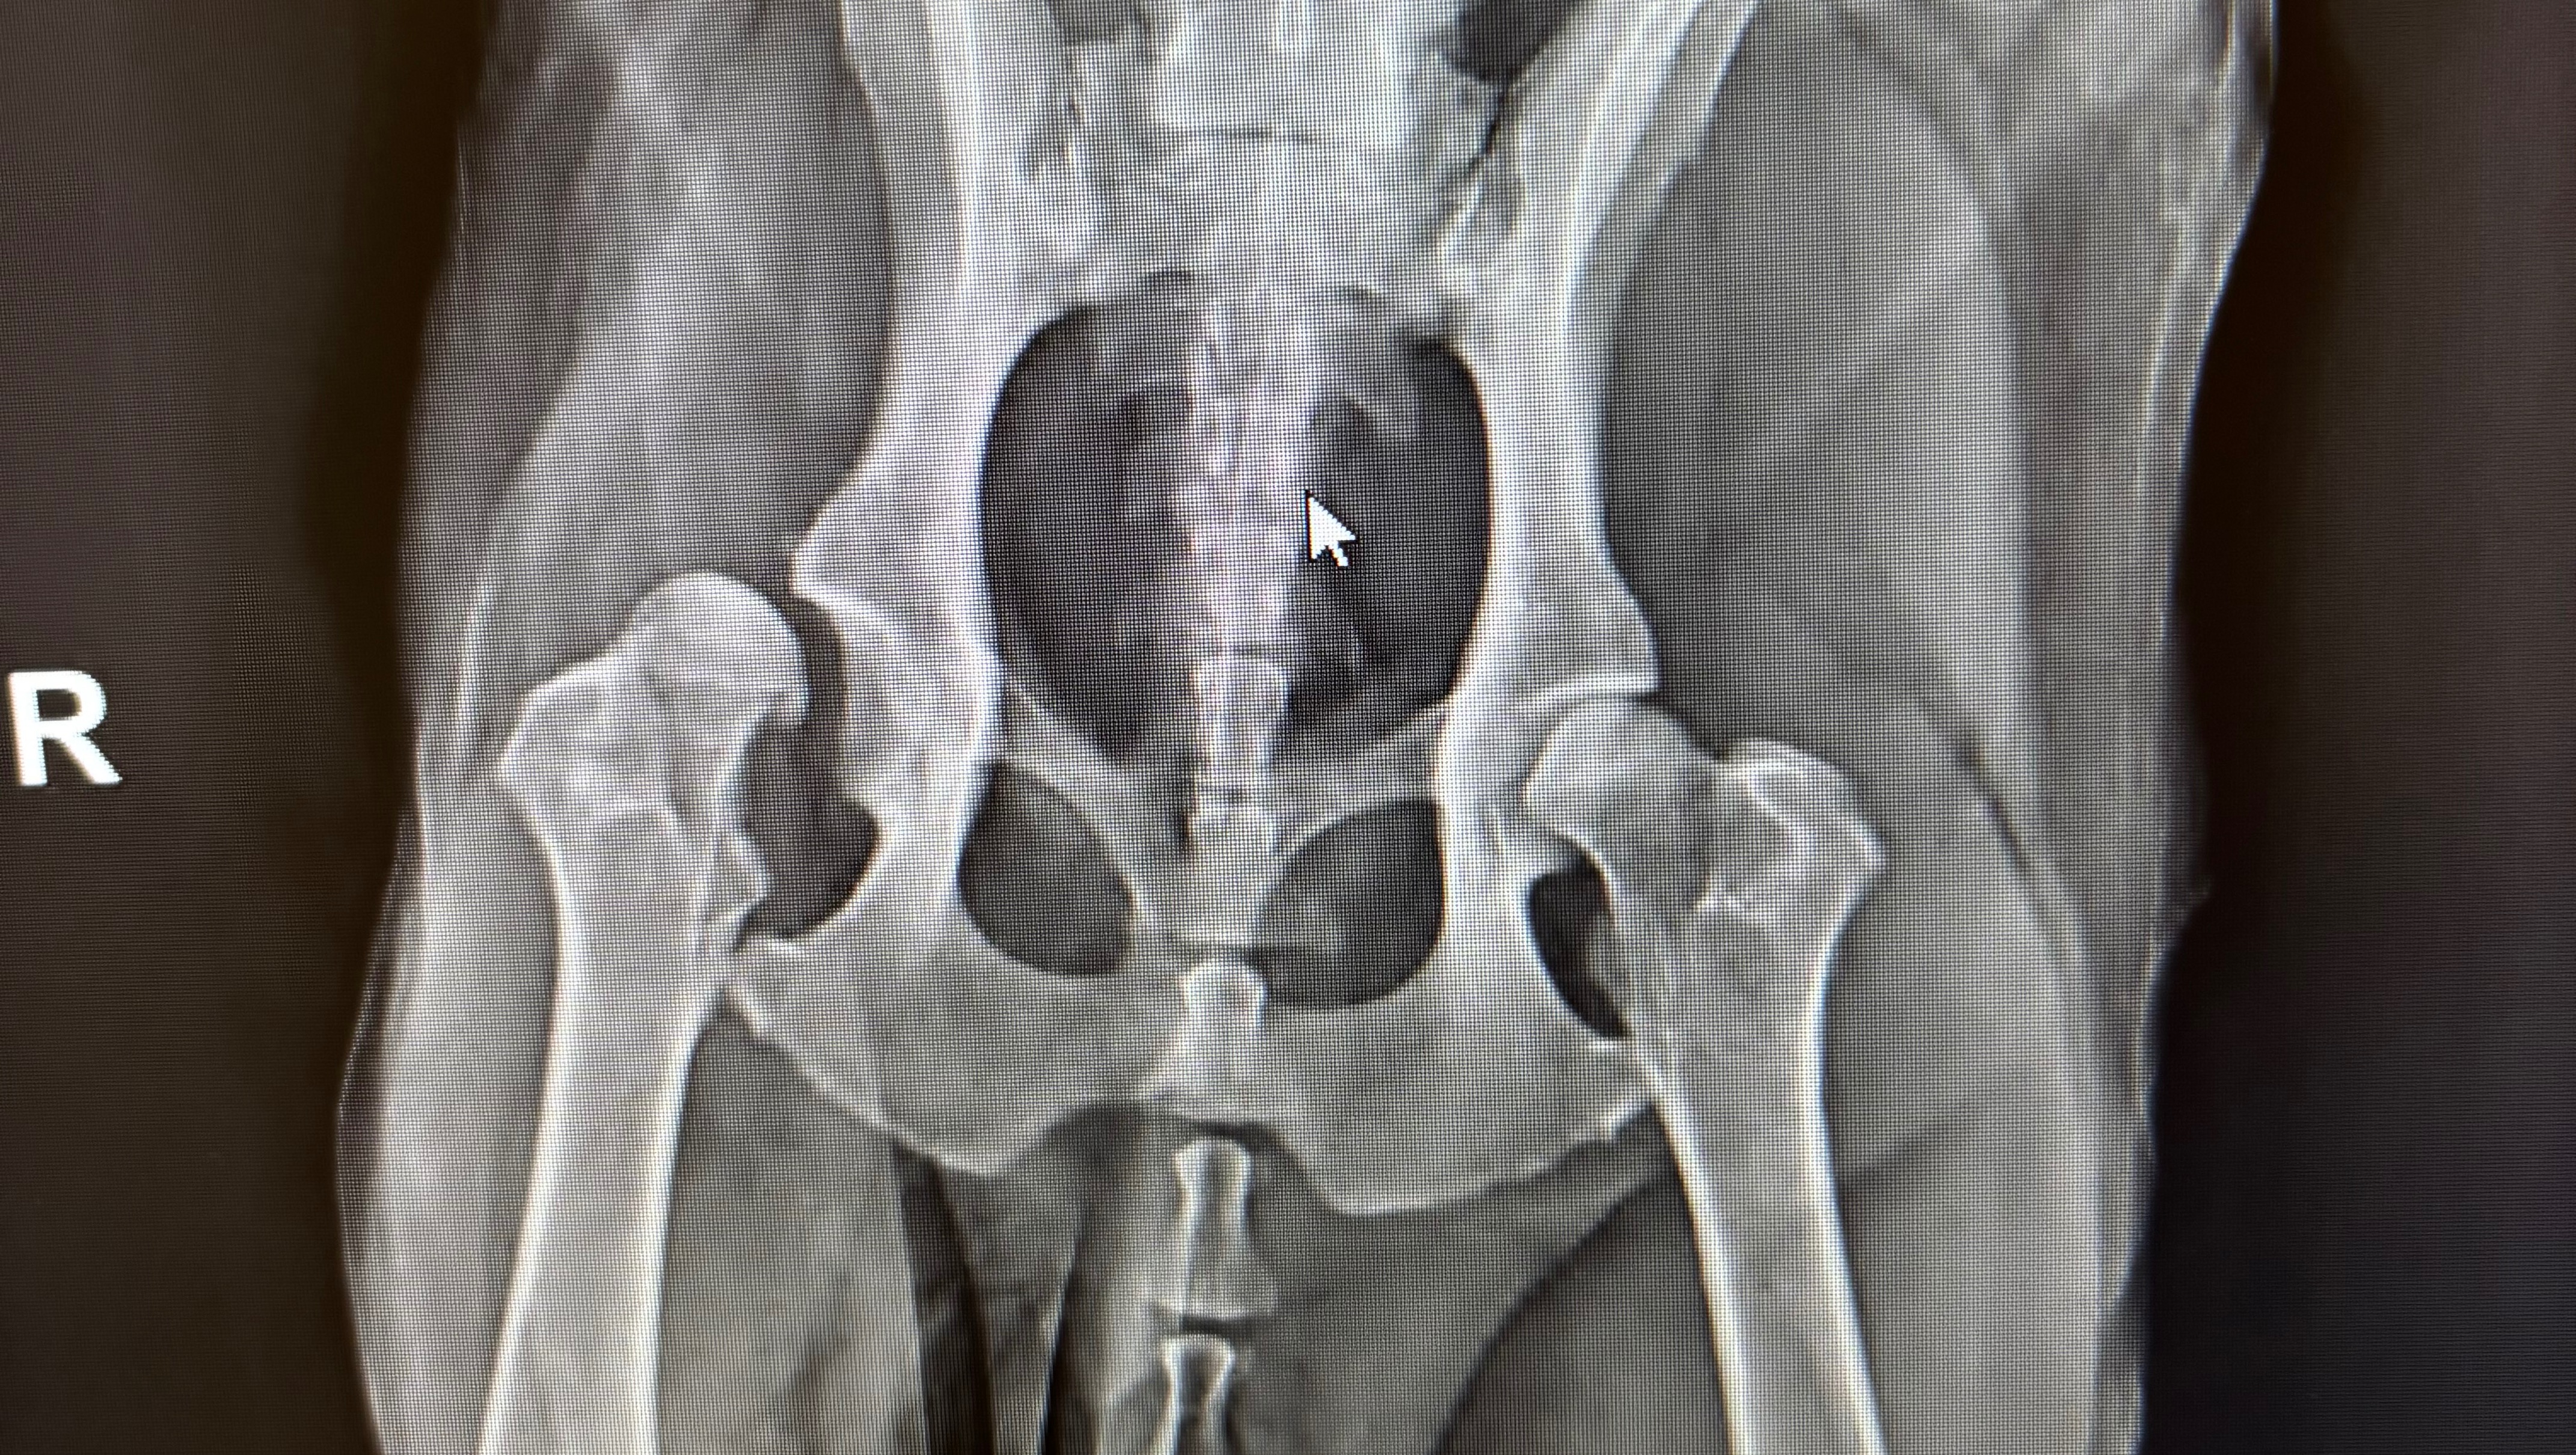

In June we noticed Winston was having a little trouble getting up and when out walking. Pretty soon he was collapsing when standing, refusing walks and is now unable to use stairs. After consults at 4 different vets and specialists he was recently diagnosed with bilateral hip dysplasia with right sided luxoid dysplasia and severe secondary osteoarthritis. Basically this means one of his hips is permanently dislocated, and there isn’t enough joint left for it to go back in, and the other hip is wearing out. Due to his size, the only real option left for him is a full hip replacement surgery at the cost of approx £12,000 not including the months of physio that will be needed after.